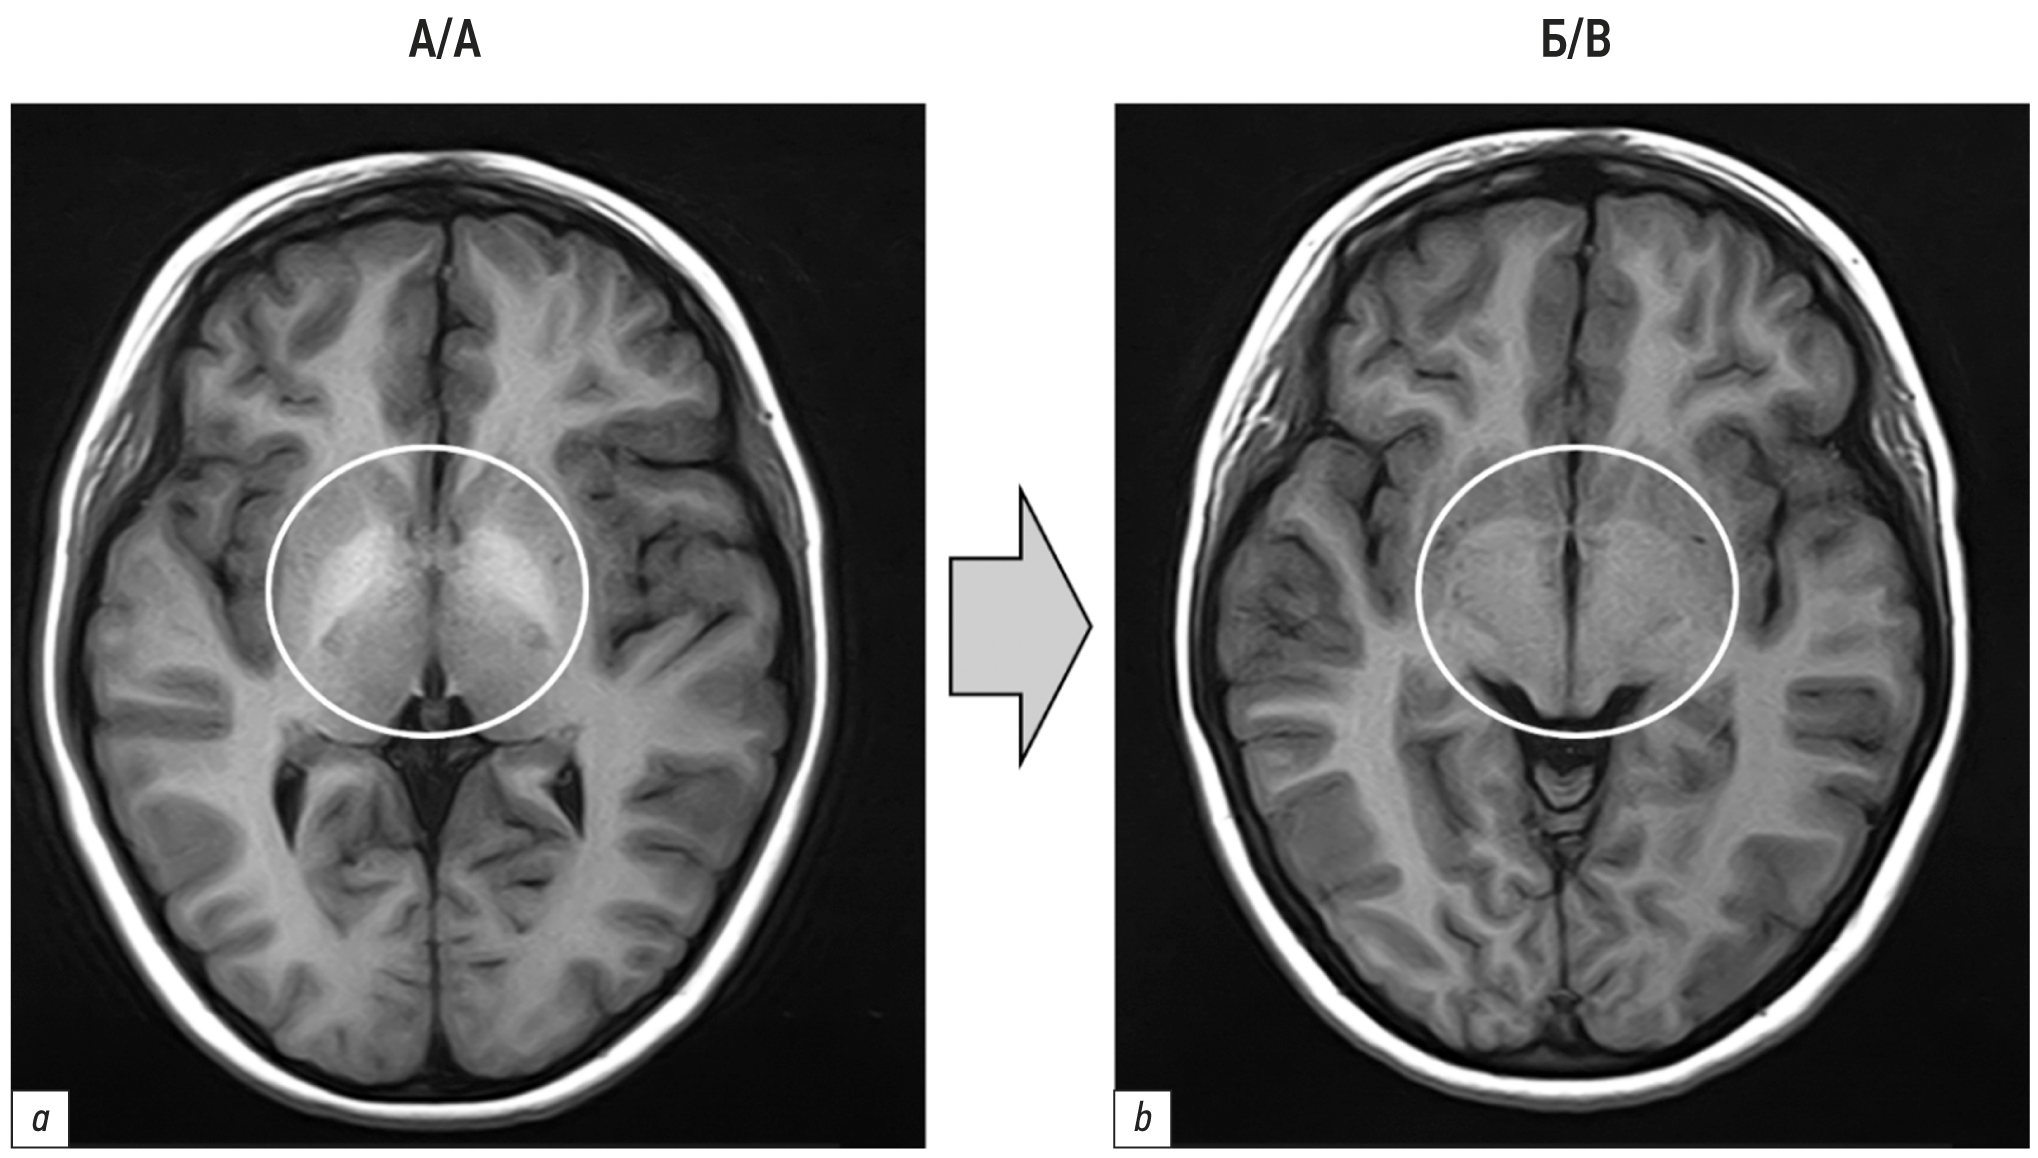

Данные МРТ головного мозга до и после реконструкции шунтов сравнивали у 16 пациентов (из них при СРА признаки накопления марганца в ЦНС наблюдались у 14). Купирование признаков ПЭ на МРТ наблюдались у 43% (6 из 14) (рис. 1).

Рис. 1. Магнитно-резонансная томограмма головного мозга (купирование признаков накопления солей марганца у мальчика 11 лет): a — до операции; отложения марганца в виде симметричных гиперинтенсивных очагов в нижней части бледного шара (круг); b — через 11 мес. после операции; бледный шар без признаков накопления солей марганца (круг).

Fig. 1. Magnetic resonance imaging of the brain (elimination of signs of manganese salt accumulation in an 11-year-old boy): a — before surgery; manganese deposits in the form of symmetrical hyperintense foci in the lower part of the globus pallidus (circle); b — 11 months after surgery; globus pallidus without signs of manganese salt accumulation (circle).

Косвенные признаки ПЭ по данным МРТ головного мозга после реконструкции СРА в ДСРА появились только у одного ребёнка (при СРА у него такие изменения по данным МРТ отсутствовали). Возможной причиной последнего может быть наличие естественного портокавального шунта у этого пациента.